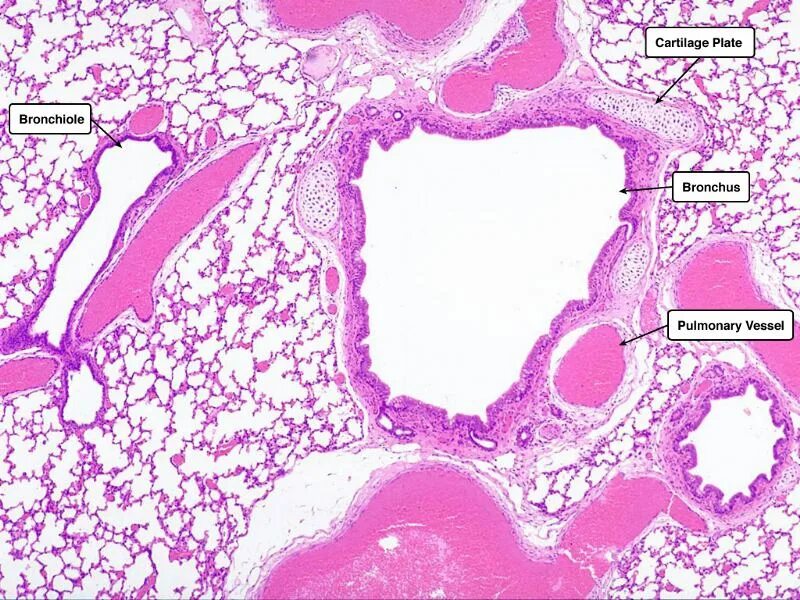

Гистологический срез это